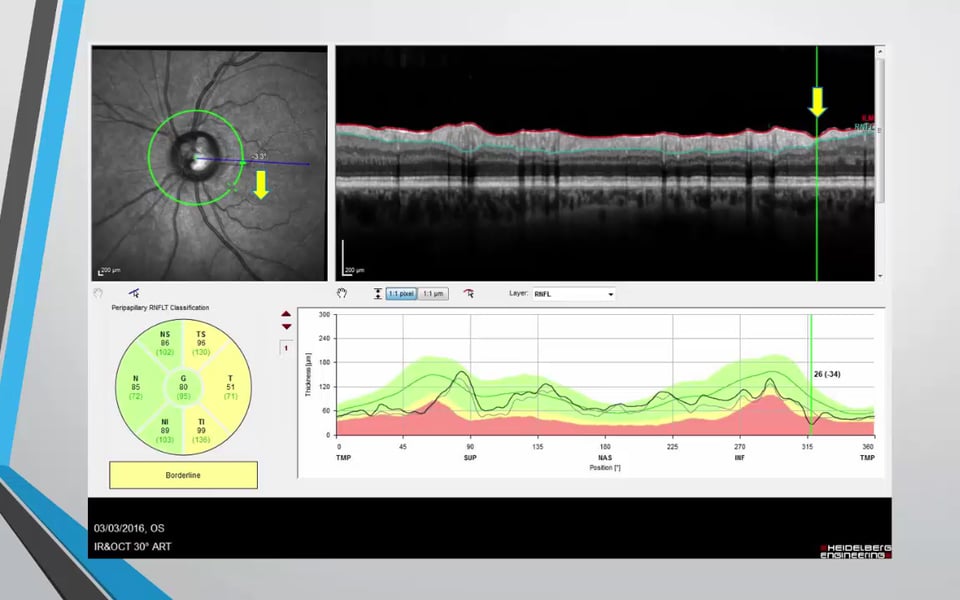

Advances in Ophthalmology - Corneal Transplantation, Cataract Surgery, Glaucoma Surgery & Vitreolysis Graham Lee 4081 Views